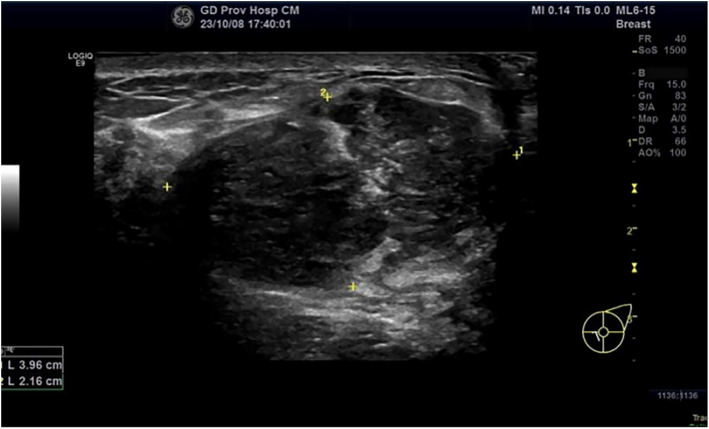

Case presentation: A 23-year-old woman presented to our hospital with a rapidly growing, palpable left breast mass. Histopathological examination of the surgical specimens (including histological features, immunohistochemical staining, and molecular analysis) confirmed the diagnosis of primary EES with EWSR1::ERG translocation in the breast. Despite receiving multimodal adjuvant therapy (surgery, chemotherapy and radiotherapy), the patient experienced two disease relapses within 15 months.